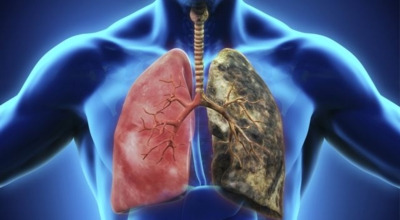

1. 금연

장기간 흡연은 기도의 보호 메커니즘을 손상시켜 기관, 기관지, 폐포 또는 폐 조직에 해를 끼쳐 폐 기능 저하에 영향을 줄 수 있습니다.